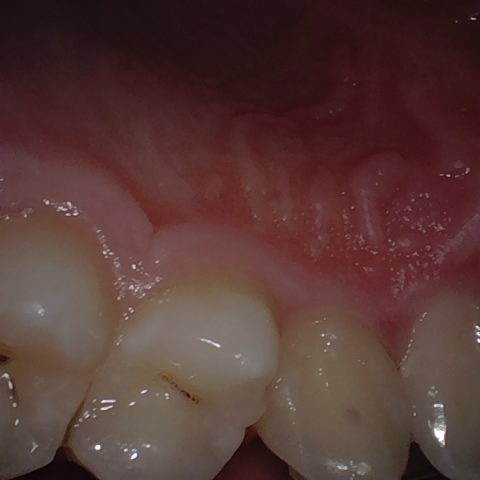

Annotated as "Good"